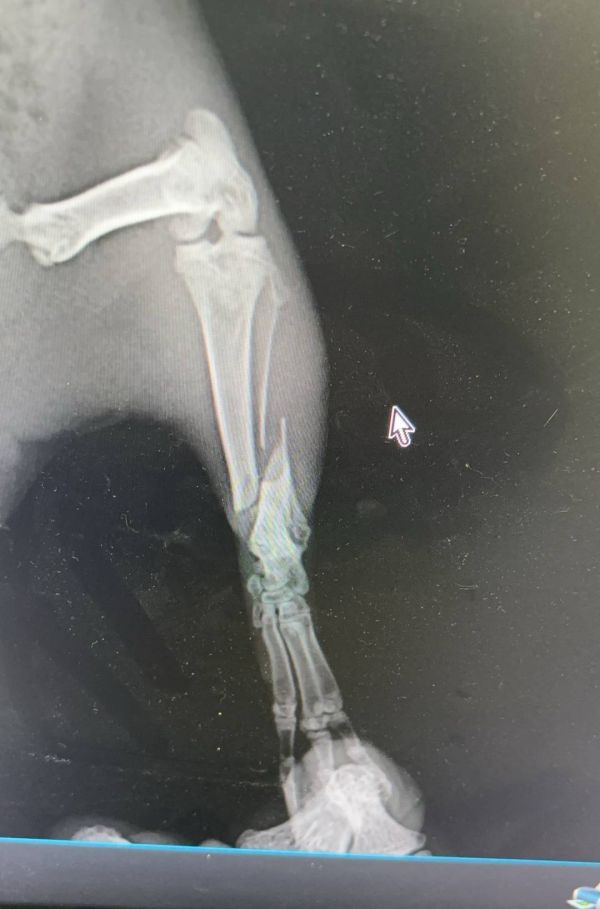

猫的骨骼整体还是比较大的,所以多数腿骨的骨折会选择内固定的方法,关节和腿骨骨裂则首选外固定,做好对接后,上夹板绑定。人古话说伤筋动骨100天,宠物其实也差不多了,猫狗的愈合速度相对快也需要45-80天的时间,根据骨折的位置和严重程度不同,恢复时间也有很大差别。

2周前上班路上,前面一辆电动自行车带着一只狗,在躲避行人的时候车猛的拐弯,车倾斜的时候狗顺势下地,后车轮从狗腿上碾过,瞬时血肉模糊。立刻用衣服铺在地上,给狗放在羽绒服上整体托起,赶快送到医院X光检查,一条腿只是表皮蹭掉一块肉,另外一条腿尺骨骨裂,颈椎和脊椎没有明显的骨裂。因为没有彻底断裂,所以没有做内固定,在外面用夹板固定,随后对皮肉伤进行消炎治疗。经过1周后精神和食欲才逐步恢复,狗狗尝试站起走路,排除脊椎受损可能,慢慢走出惊吓的阴影,这如果压过的是脖子或者脊椎,面临的可能就是后半生的瘫痪了。